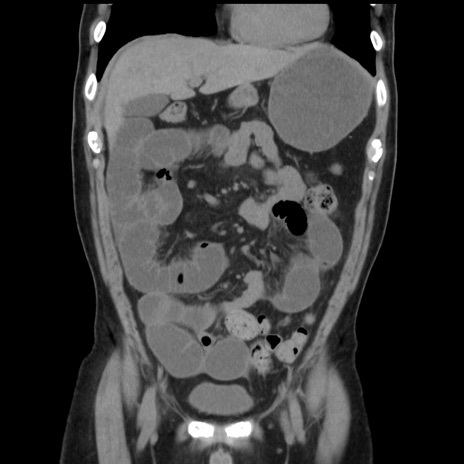

症例16(冠状断像)

【症例】 70歳代男性

【主訴】 腹痛、嘔吐

【現病歴】 約1ヶ月前より間欠的に腹痛と嘔吐あり、当院消化器内科を受診したところCTで多発する肝臓のLDAを指摘され、精査中であった。以降は消化器症状は安定していたが、2日前より嘔気と腹痛があり、同日より排便・排ガスが消失した。改善認めず、 本日、救急外来を受診した。

【既往歴】 大腸ポリープ切除後。

【身体所見】意識清明・会話良好、BT 36.3℃、BP 127/80mmHg、 P 80bpm、腹部:膨満あり、平坦・軟、上腹部正中および下腹部正中に圧痛あり、反跳痛なし、筋性防御なし。

【データ】WBC 7200、CRP 0.77